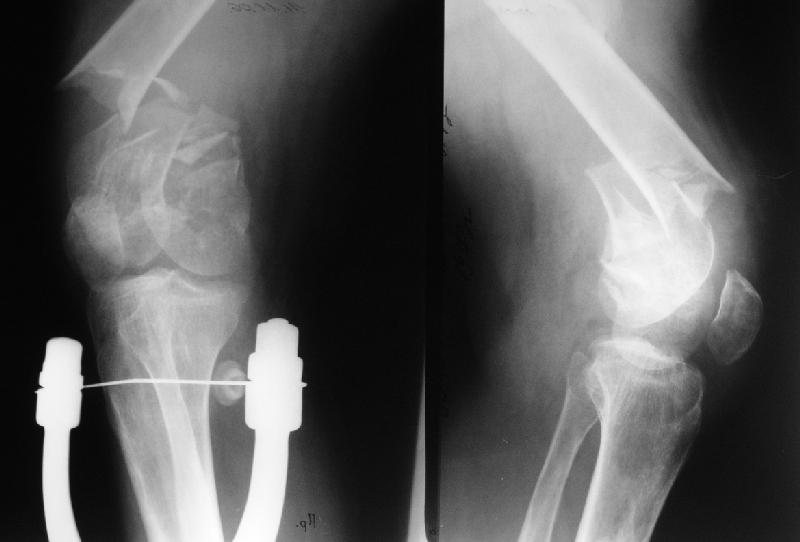

It appears to me that the neck femur and shaft femur are old injuries. I would give preference to the distal femur fracture, but you can only align

the shaft if the malunited midshaft femur fracture is corrected. So my plan:

1. Open reduction and plating of the midshaft femur fracture

2. Distal femur fracture reduction and fixation by indirect reduction if possible, direct reduction if required. I would use locking plate if possible, if not distal femur plate.

Больной поступил в клинику. Дополнительные сведения: диафизарный перелом (открытый)получил 5 лет назад - падение с 5 этажа. Лечился консервативно. Через год стал ходить без трости, хромоты не было, колено гнулось ( со слов больного),В принципе был удовлетворен своим состоянием. 1,5 месяца назад упал в подъезде (в состоянии алкогольного опьянения). Отказался от 2 группы инвалидности - просто не пошел на переосвидетельствование. Живет с мамой (пенсионерка).

Я рекомендую разделить лечение на этапы первым этапом заняться переломом дистального бедра. На мой ввзгляд Дистальныый бедренный гвоздь, введённый через колено - оптимальное решение вопроса. Если нет - плата и шурупы.

после заживления перелома , вторым этапом либо артродез т.б сустава с корригирующей остеотомией, либо протезирование длинным протезом с коррекцией малюниона.

Зная тебя, уверен, что на первом этапе ты сделаешь открытую репозицию перелома дистального бедра с коррегирующей остеотомией с фиксацией длинным гвоздём или платой. Успехов!